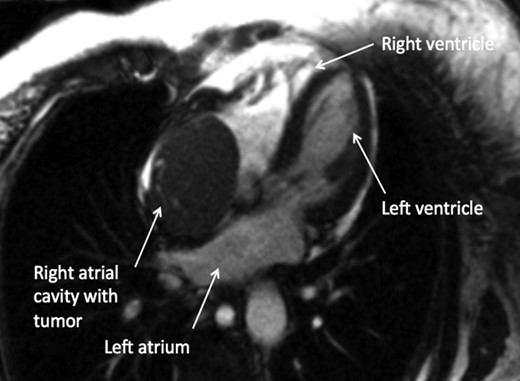

A 74-year-old female presented with facial and upper extremity swelling over the last month. The swelling was worse in the morning and improved throughout the day. The patent also reported dyspnea on exertion. A review of systems was otherwise negative. Social history was notable for 40-pack-year smoking history, but she quit smoking 12 years ago. Her vital sign were stable. Physical examination revealed mild facial swelling, non-pitting edema of the upper extremities and distention of superficial veins of the anterior chest wall and jugular veins. There were no significant laboratory abnormalities. An echocardiogram showed moderate right atrial dilation with a mobile mass in the atrial cavity prolapsing through the tricuspid valve, bowing of atrial septum from right to left consistent with increased right atrial pressure, moderate tricuspid regurgitation and normal left ventricular ejection fraction with no regional wall motion abnormalities. Cardiovascular magnetic resonance imaging revealed a 9.9 × 4.3 cm heterogeneous mass admixed with thrombus in the anterior mediastinum compressing the SVC and endovenously extending into the right atrium (Figs 1–3). Anticoagulation with heparin drip was initiated. A computed tomography (CT)-guided biopsy revealed a tan-colored mass with CD5 lymphocyte predominance, inconspicuous epithelial cells positive for P63 expression and cytokeratin AE1/AE3 that was morphologically consistent with thymoma type B1.

CMR axial four-chamber view: mass in the right atrial cavity protruding through the tricuspid valve into the right ventricle.